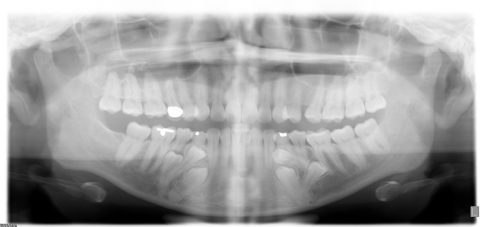

Adult orthodontics has become more popular especially after the introduction of cosmetic treatment options such as InvisalignⓇ. Orthodontic treatment can be performed at any age as long as the teeth and gums are healthy. There are, however, special considerations when it comes to adult braces. Adults usually have more restorations, root canals, crowns, dental implants, veneers, missing teeth and/or periodontal disease. There are also certain medical conditions and medications that can affect your orthodontic treatment. For example, bisphosphonates taken for osteoporosis can slow down tooth movement substantially.

Adult orthodontics often require a collaboration with your dentist or other dental specialists. We will gladly coordinate and work closely with your dentist to ensure best treatment results. Orthodontic treatment may be recommended by your dentist to facilitate certain dental procedures. As an example, orthodontics can be used to open a larger space for an implant placement. Another example is using Invisalign in preparation of cosmetic bonding or veneers. Those cases can be very rewarding and treatment outcomes are quite spectacular.